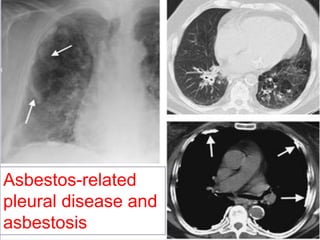

Rule no. 2

Asbestos-related

pleural disease and

asbestosis

Associated pleural thickening and/or

calcification suggest asbestosis.

Rule no. 5